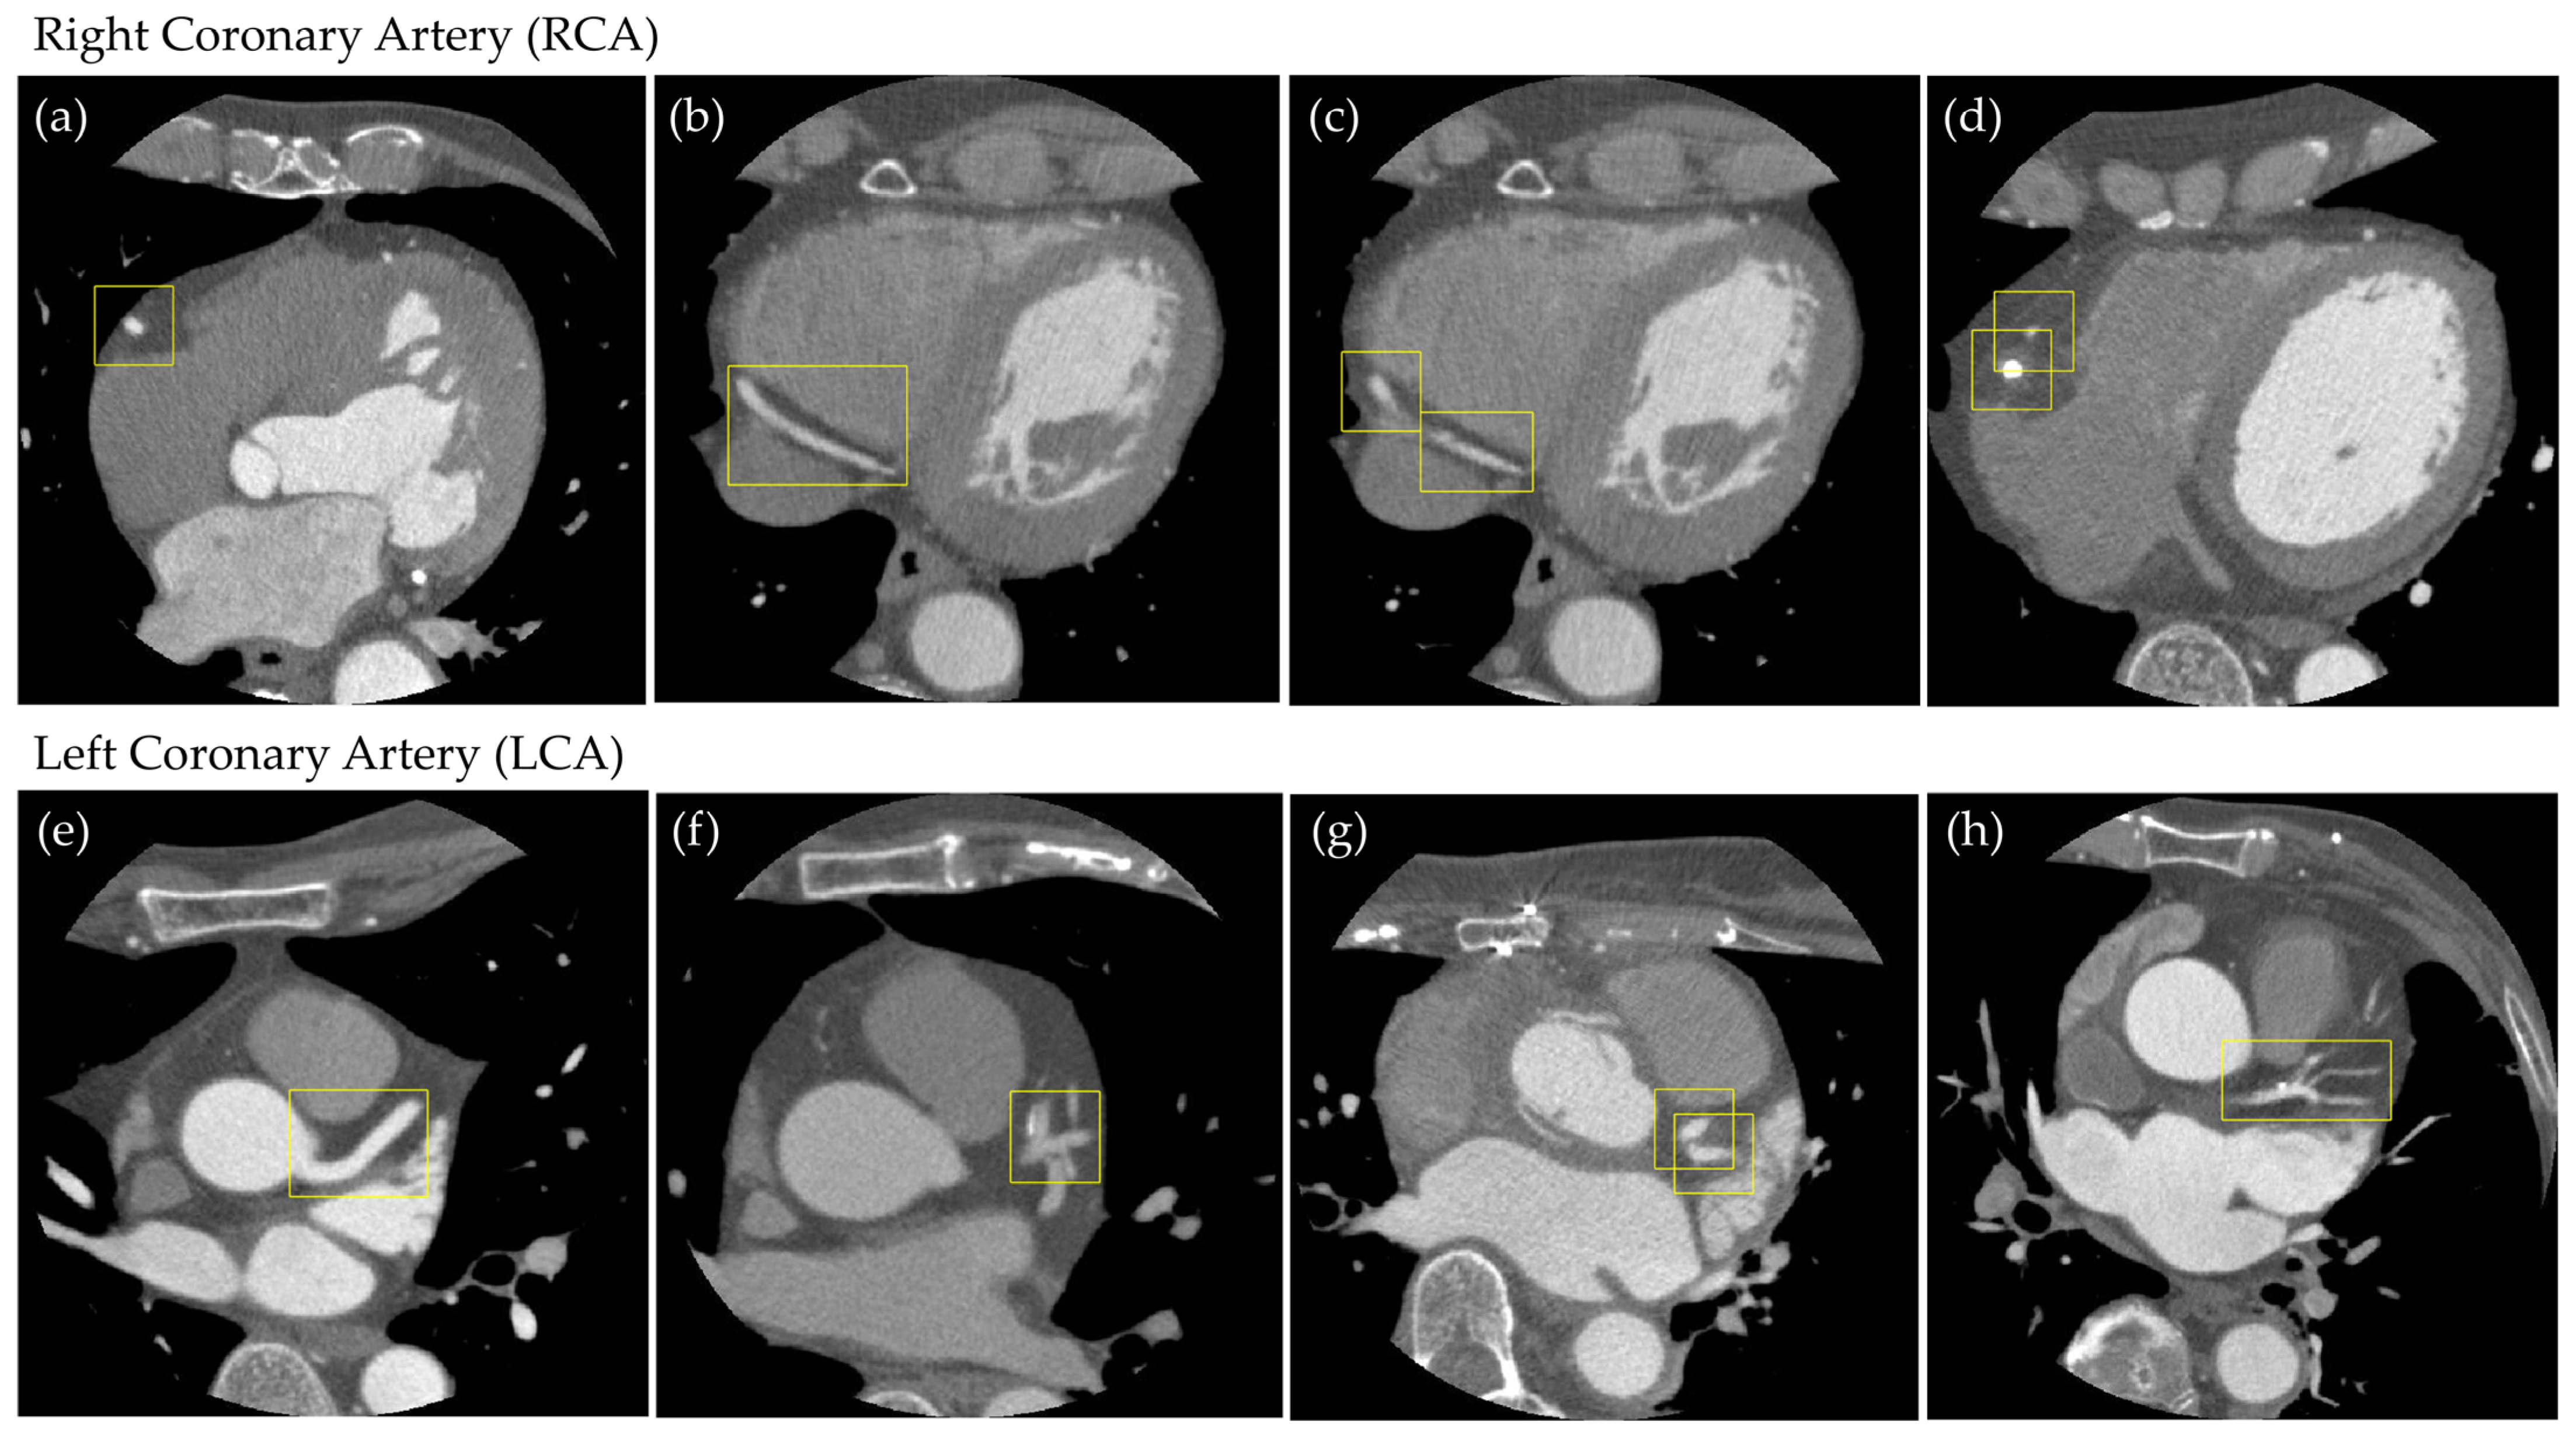

2.3. Supervised Data Creation

Object Detection